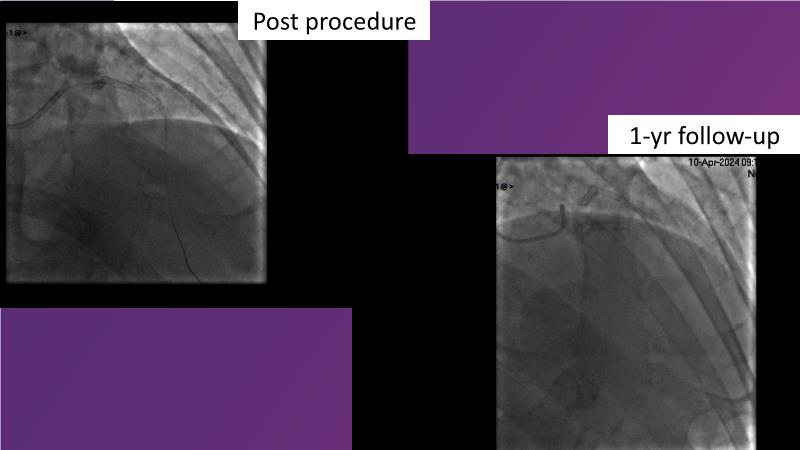

Browse this EuroPCR 2024 session to explore the safety and efficacy of sirolimus-coated balloons from pre-clinical data, review MagicTouch data from real-world populations with case-based examples, and learn about the MagicTouch sirolimus-coated balloon clinical programs. Discover insights and takeaways from the significance of the EASTBOURNE subgroups, and analyze the challenges and opportunities in PCI for diabetic patients.

- To learn from the real world registries and complex cases to understand the practical implications and potential of the device in diverse patient population